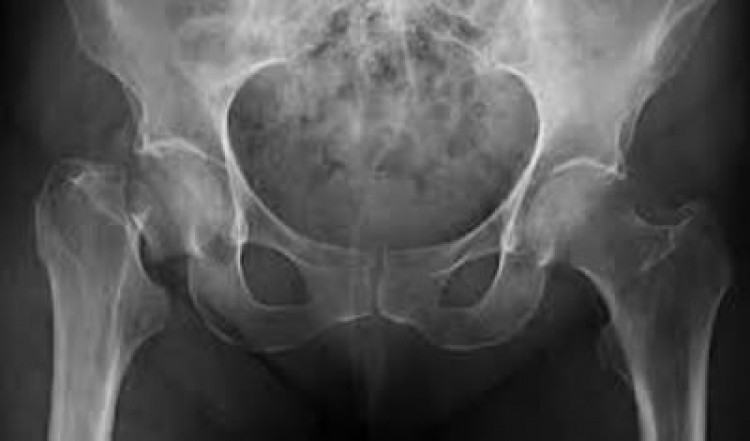

La osteoporosis es una enfermedad crónica y progresiva que afecta a los huesos, como consecuencia los huesos se vuelven frágiles y pueden llegar a producirse fracturas por caídas simples o realizando actividades que requieren de un esfuerzo mínimo.

En México, las fracturas más comunes son la de muñeca, cadera, columna y húmero. Estudios afirman que las personas que han tenido una fractura a causa de la osteoporosis aumentan en un 87%, la probabilidad de tener una segunda fractura en el futuro.